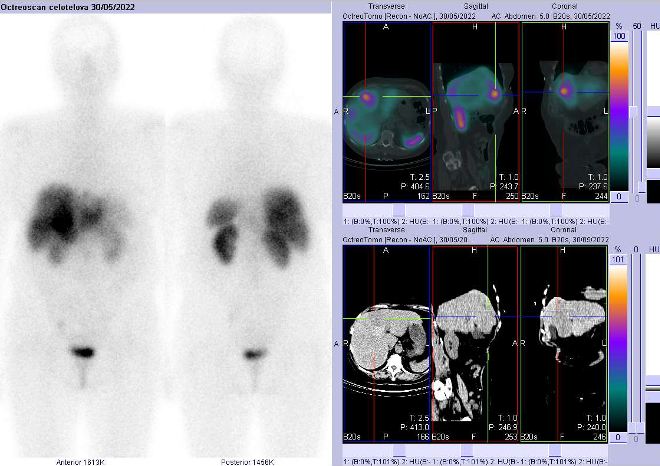

/ Obr. č.

2: Celotělová scintigrafie a fúze SPECT/CT 4 hod. po aplikaci OctreoScanu. Zaměřeno na pravý jaterní lalok s ložiskem.

/

Pozorujeme patologické ložisko zvýšené depozice radiofarmaka v segmentu S4 pravého jaterního laloku, ve dvou uzlinách – jedné nad bránicí a druhé pod levým jaterním lalokem a v pánvi na rozhraní levé kosti kyčelní a kosti křížové, nález svědčí pro tkáň se zvýšenou denzitou somatostatinových receptorů.

Závěr:

U 68leté ženy s neuroendokrinním tumorem nejasného primárního zdroje prokazujeme generalizaci v játrech, uzlinách a skeletu.